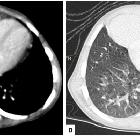

Unusual

association of parvo-virus with Morgagni hernia, mistaken for patch of consolidation. Axial mediastinal (A) and lung (B) window showed a homogenous soft tissue density in RT cardio-phrenic angle abutting and displacing the pericardium and RT ventricle with clear interface. Sharp delineation with lung parenchyma is noted.